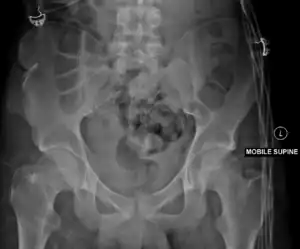

Duverney fractures can usually be seen on pelvic X-rays, but CT scans are required to fully delineate the fracture and to look for associated fractures involving the pelvic ring.[3]